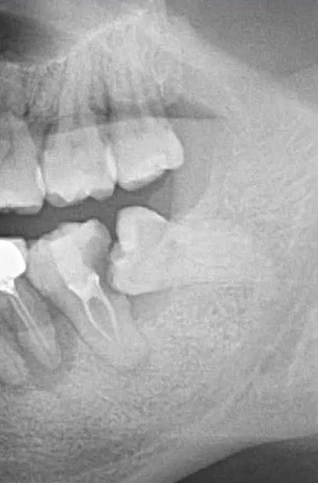

【病例1】

9岁,男孩,因右上面颊部肿胀来源就诊

55深龋→根尖炎→面颊肿胀

根尖片视野范围较小,曲断检查结果:乳5颌骨根方有含牙囊肿的存在。

曲面断层片怎么看口腔精读 | 一次性教你看懂曲面断层片!_https://www.jmylbn.com_新闻资讯_第28张